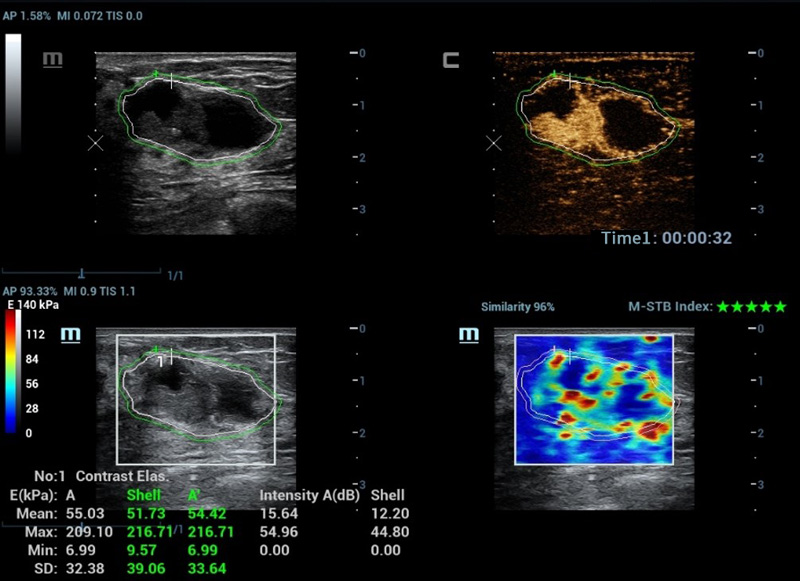

M-Reference Multi-parametrische analysetools

M-Ref. C&E

M-Ref. C&E Borst kwaadaardig

M-Ref. C&E ondersteunt het weergeven van het contrast en de STE in ├®├®n vlak voor vergelijkende beoordeling van perfusie en elasticiteit.

M-Ref. E Compare

M-Ref. E Compare Borst kwaadaardig

M-Ref. E Compare ondersteunt het weergeven van zowel de realtime strain-elastografie als STE in ├®├®n vlak voor de evaluatie van weefselstijfheid.

Geavanceerde CEUS

Nieuwe CEUS-kwantificatieanalyse

Nieuwe CEUS QA Borst kwaadaardig

De tijd-intensiteitscurve maakt kwantitatieve analyse van CEUS-beeldvorming mogelijk. De nieuwe CEUS QA biedt tools voor geavanceerde kwantitatieve analyse die ondersteuning bieden bij tumorbeoordelingen en klinisch onderzoek.

Strain-elastografie

- Hoge gevoeligheid, productiviteit, penetratie en nauwkeurigheid

- Unieke 'schil' voor de analyse van het infiltratiegebied van de tumor

Strain-elastografie